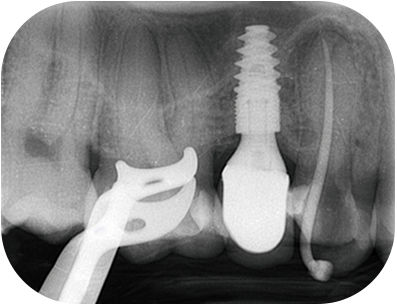

Le traitement endodontique sera finalisé par une restauration en composite collé dans la séance, et la réalisation d’une couronne sera indiquée afin de maximiser les chances de succès à long terme(5).

Radio post-opératoire après collageFig. 09 : radio per-opératoire après collage.

Le pronostic endodontique est bon car nous avons identifié et traiter la cause de l’infection.

Le pronostic mécanique est plus réservé mais reste acceptable, la fêlure ne semblant pas s’être propagée plus apicalement cliniquement et lors de l’analyse 3D(6). Associée à la restauration prothétique réalisée par le correspondant, cette dent présente encore de belles années(7).